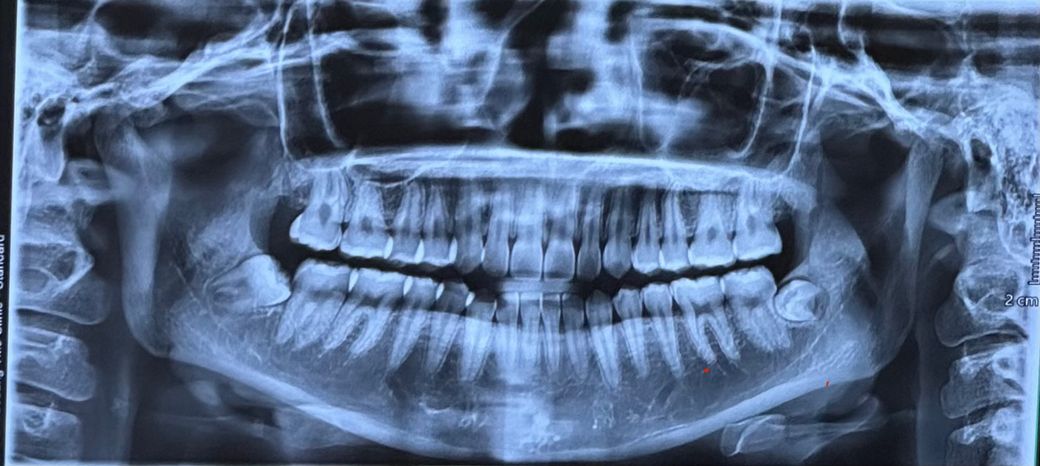

첫번째 사진이 최근이고 두번째가 일년전인데요

• 2번 째 사진

파노라마는 턱관절을 관찰하기에 적절한 방사선사진은 아닙니다만 위 사진상에는 괜찮아보입니다.

엑스레이 상으로는 턱관절 과두가 날카롭게 보이긴 합니다. 정확한건 치과에 가셔서 턱관절 CT를 찍어보셔야될것같습니다.

1. 턱관절엔 큰 변화나 병적인 양상은 없어보입니다

2. 어떤 통증을 느끼시는지 명확히 서술되진 않았으나 꼭 턱관절 때문이 아니라도 왼쪽 아래 매복 사랑니때문에 턱 통증, 입 안벌어짐, 씹을때 통증 등이 있을 수도 있습니다